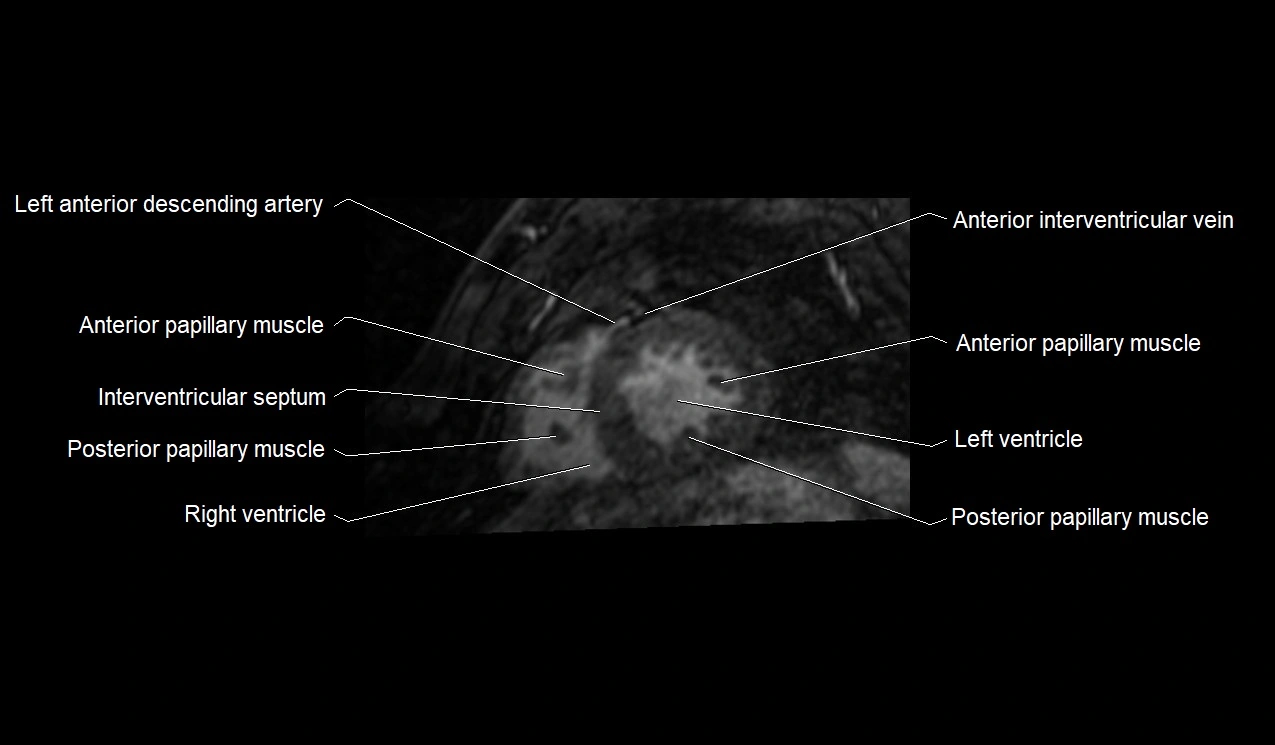

- Anterior papillary muscle

- Interventricular Septum

- Posterior papillary muscle

- Left ventricle

- Right ventricle